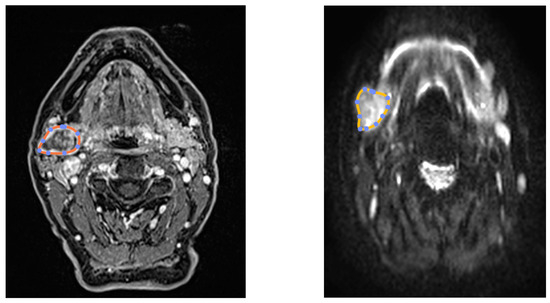

3.1. ROI Selection and Parametric Maps